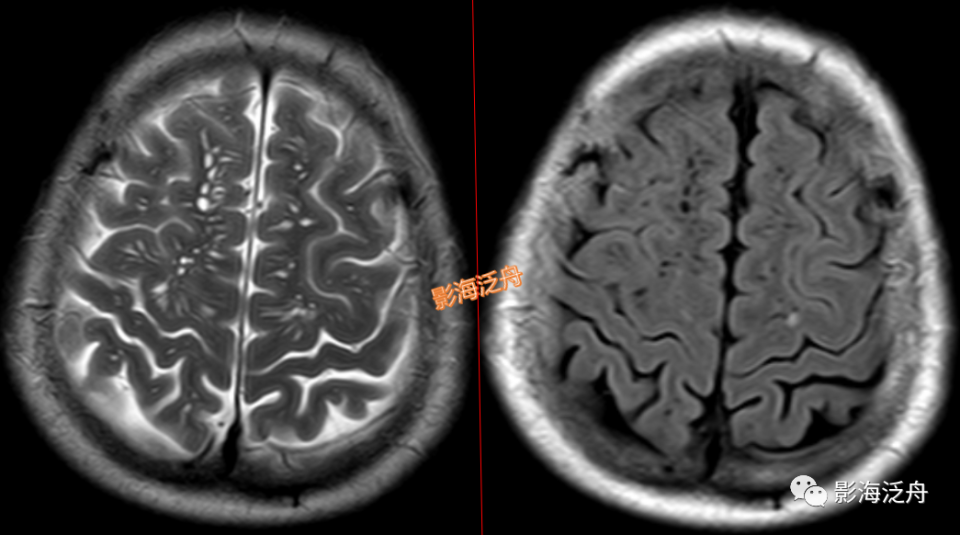

当脱髓鞘改变呈片状且沿着侧脑室周围对称性分布时,大家往往一眼就能识别出来,像上图这种双侧半卵圆中心多发非特异性脱髓鞘病灶,大家可能就有点心虚了。注意最大的一个病灶(黄箭)长轴平行于侧脑室(红线),所以只是普通的退变,而不是不是MS。

当这种非特异性脱髓鞘病灶比较局限、散发的时候,如何与VR腔隙及腔梗灶区分呢?一般来说,前者显示比后两者更加浅淡和模糊,在T1WI序列尤为明显。